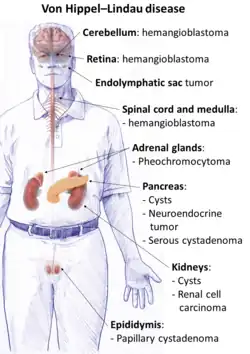

| Locations of the main types of cysts and tumors in Von Hippel–Lindau disease.[2] | |

Conditions associated with VHL disease include angiomatosis, hemangioblastomas, pheochromocytoma, renal cell carcinoma, pancreatic cysts (pancreatic serous cystadenoma), endolymphatic sac tumor, and bilateral papillary cystadenomas of the epididymis (men) or broad ligament of the uterus (women).[7][8] Angiomatosis occurs in 37.2% of patients presenting with VHL disease and usually occurs in the retina. As a result, loss of vision is very common. However, other organs can be affected: strokes, heart attacks, and cardiovascular disease are common additional symptoms.[6] Approximately 40% of VHL disease presents with CNS hemangioblastomas and they are present in around 60–80%. Spinal hemangioblastomas are found in 13–59% of VHL disease and are specific because 80% are found in VHL disease.[9][10] Although all of these tumors are common in VHL disease, around half of cases present with only one tumor type.[10] Most people with VHL develop symptoms in their mid-twenties.[11]